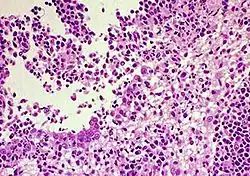

| FIP-infected kidney showing inflammatory response | |